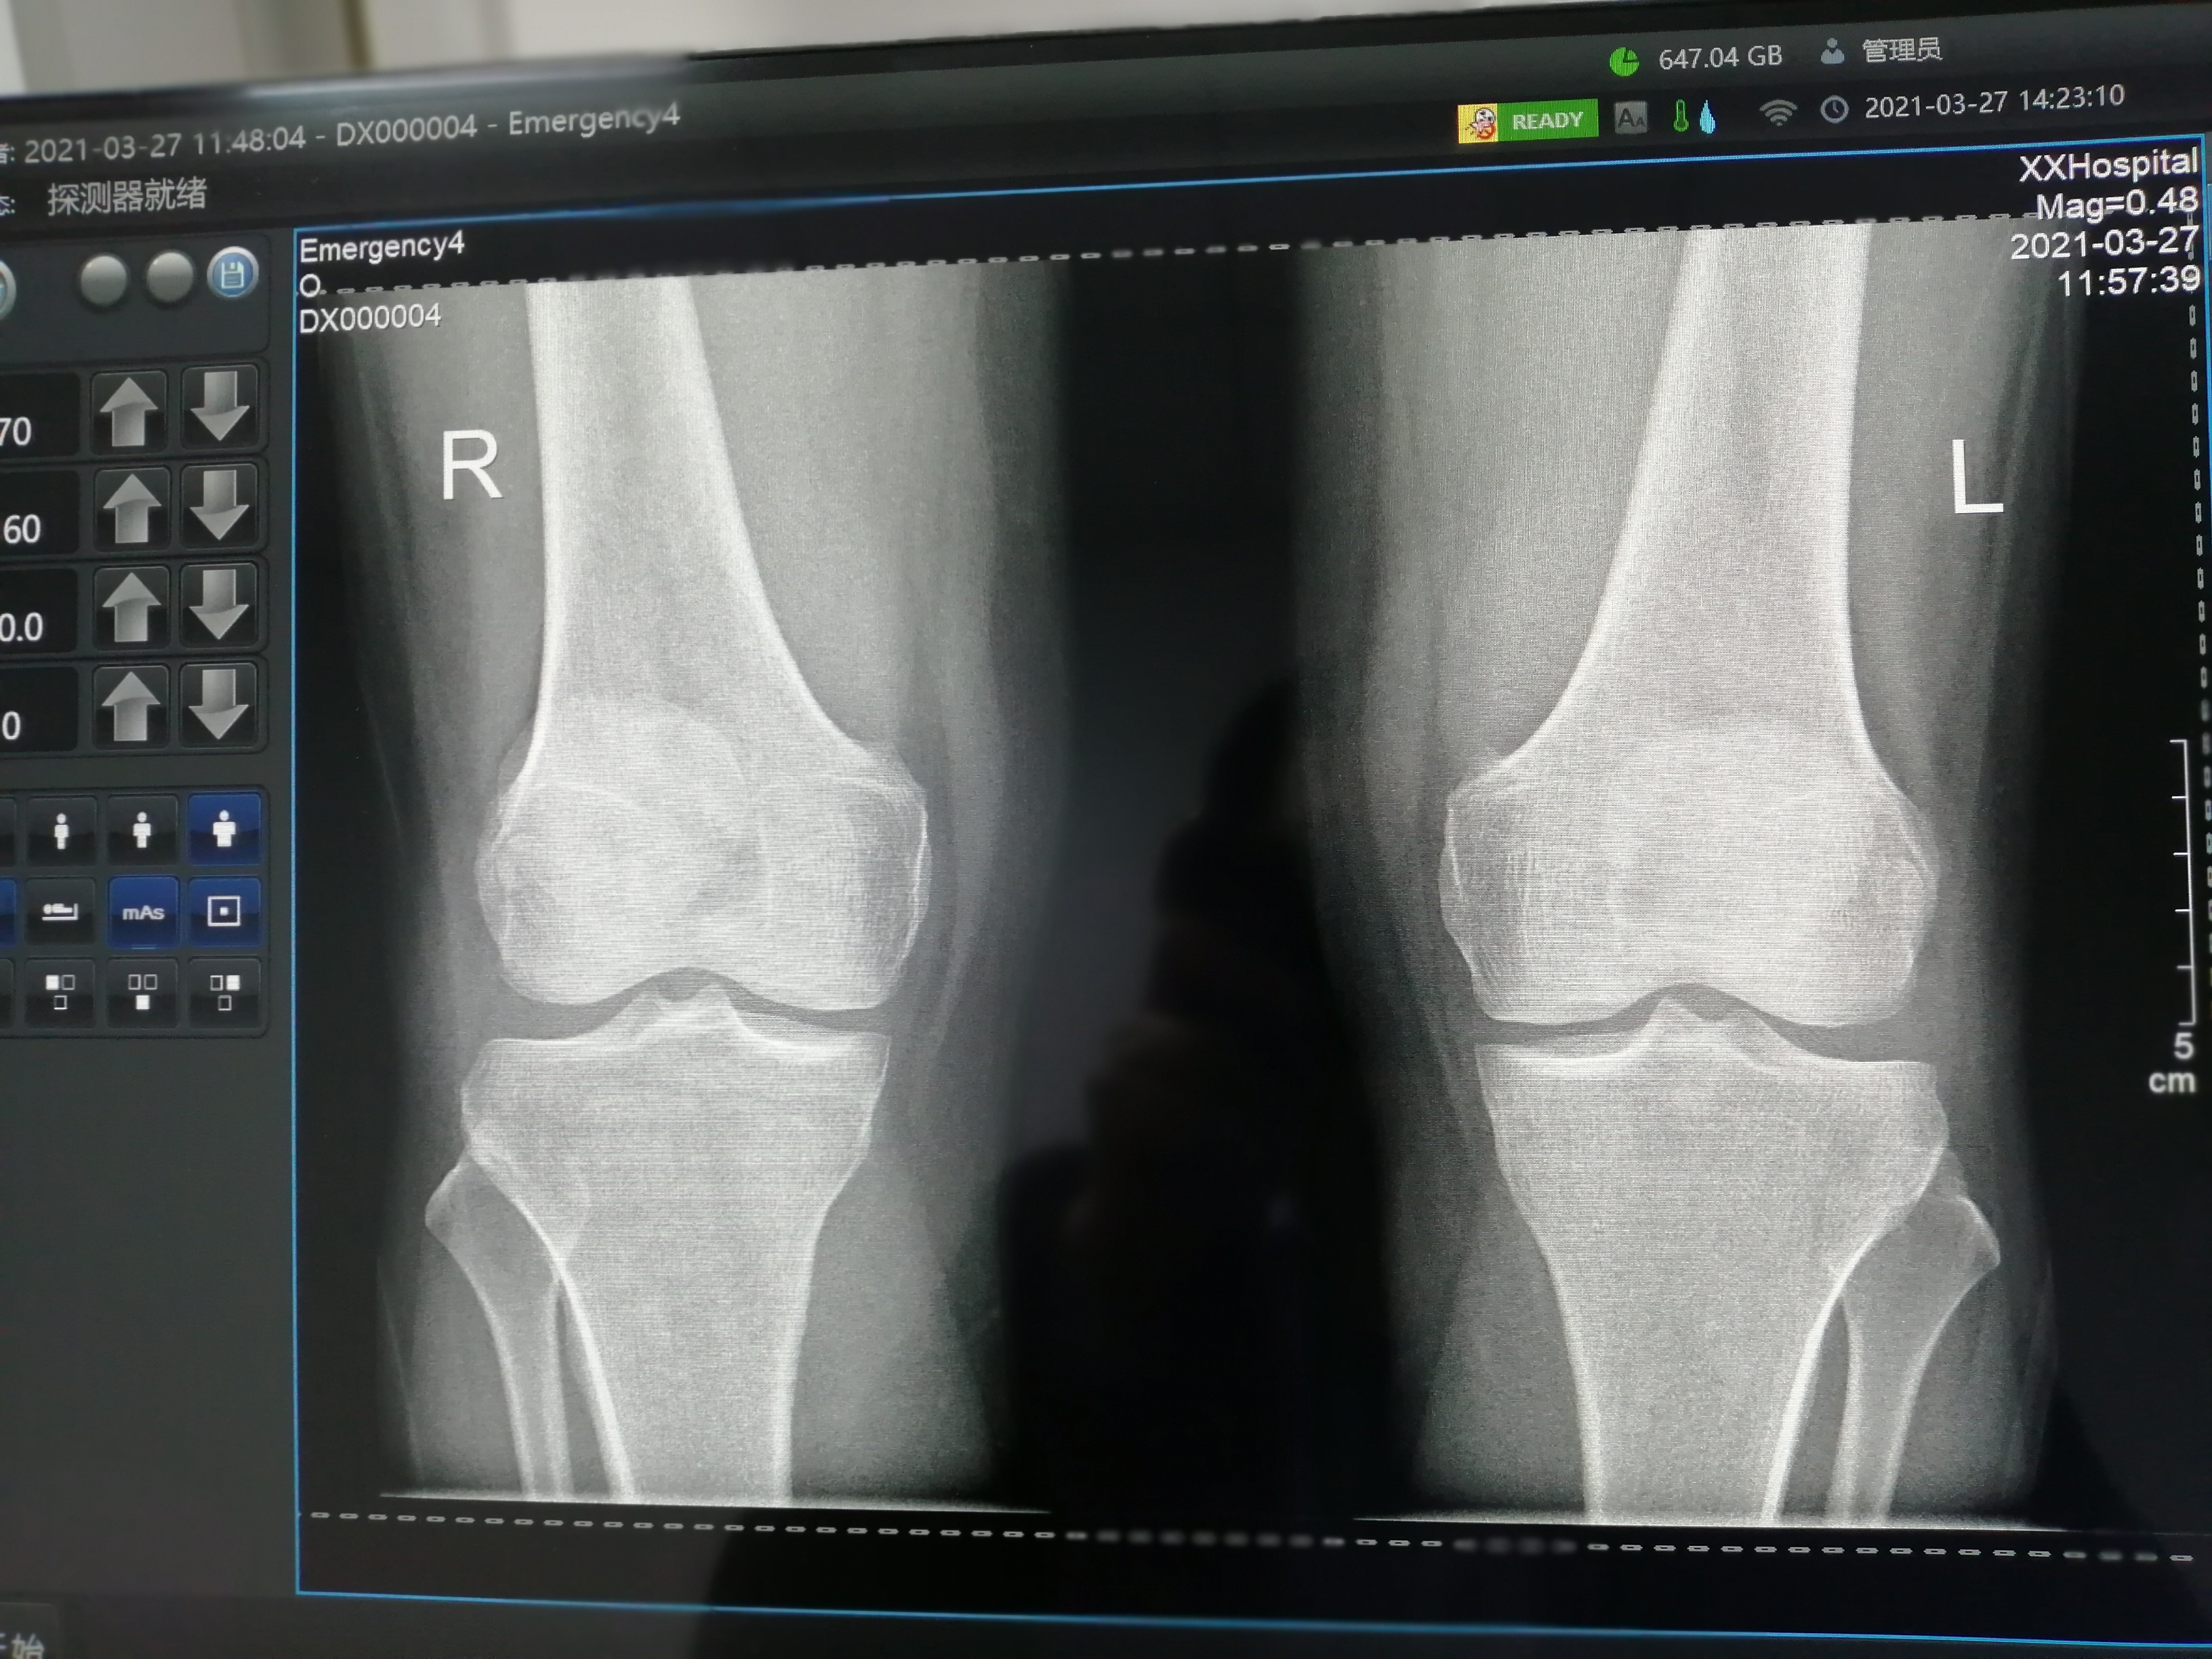

图像中的白色区域过度扩张,原本应该有一定灰度层次的部位全部变成了耀眼的白色。比如,在拍摄骨骼较为密集的部位时,骨头可能会呈现出完全的白色块状,失去了骨小梁等内部结构的显示。

一些含有钙质的组织或异物会因为过曝而失去其原本的形态特征,变得难以辨认。例如,钙化的淋巴结在过曝的图像中可能只是一个模糊的白色斑点,无法判断其大小和位置。

整个图像呈现出一种灰暗的色调,缺乏足够的对比度和清晰度。组织和器官的轮廓变得模糊不清,难以分辨其边界和形态。例如,肝脏、脾脏等实质性器官在欠曝的图像中可能只是一团灰暗的阴影,无法看清其内部结构。

欠曝可能导致重要的诊断信息丢失。比如,在胸部 X 光检查中,肺部的纹理和病变可能因为图像过暗而难以观察到。对于骨折患者,欠曝的 X 光图像可能无法清晰显示骨折线的位置和程度。